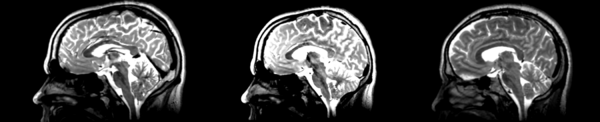

Different subject registration

- 01053-t2 -> 01031-t2 = Result. All the images shown have the moving image on the left, the resultant image in the middle, and the target image on the right.

Rigid

01053>01031rigid.png = not bad... different brains of different sizes, but seem to be aligned in the ventricles so output seems okay. output slightly blurry. bad initial leveling displays.

Linear

01053>01031linear.png = not bad... different brains of different sizes, but seem to be aligned in the ventricles so output seems okay.output slightly blurry. bad initial leveling displays.

Affine

01053>01031_affine.png = looks good in terms of size. odd warping of frontal lobe and cerebellum area, but otherwise good coregistration.